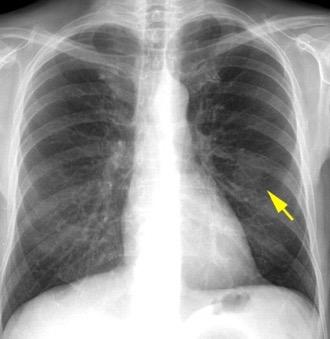

Derrame pleural 43-48% de pacientes con embolismo.

< 1/3 de hemitórax: 90%.(puede haber en lado opuesto).

Siempre exudados.

75% de los pacientes con TEP y derrame pleural tienen dolor pleurítico.

La disnea desproporcionada